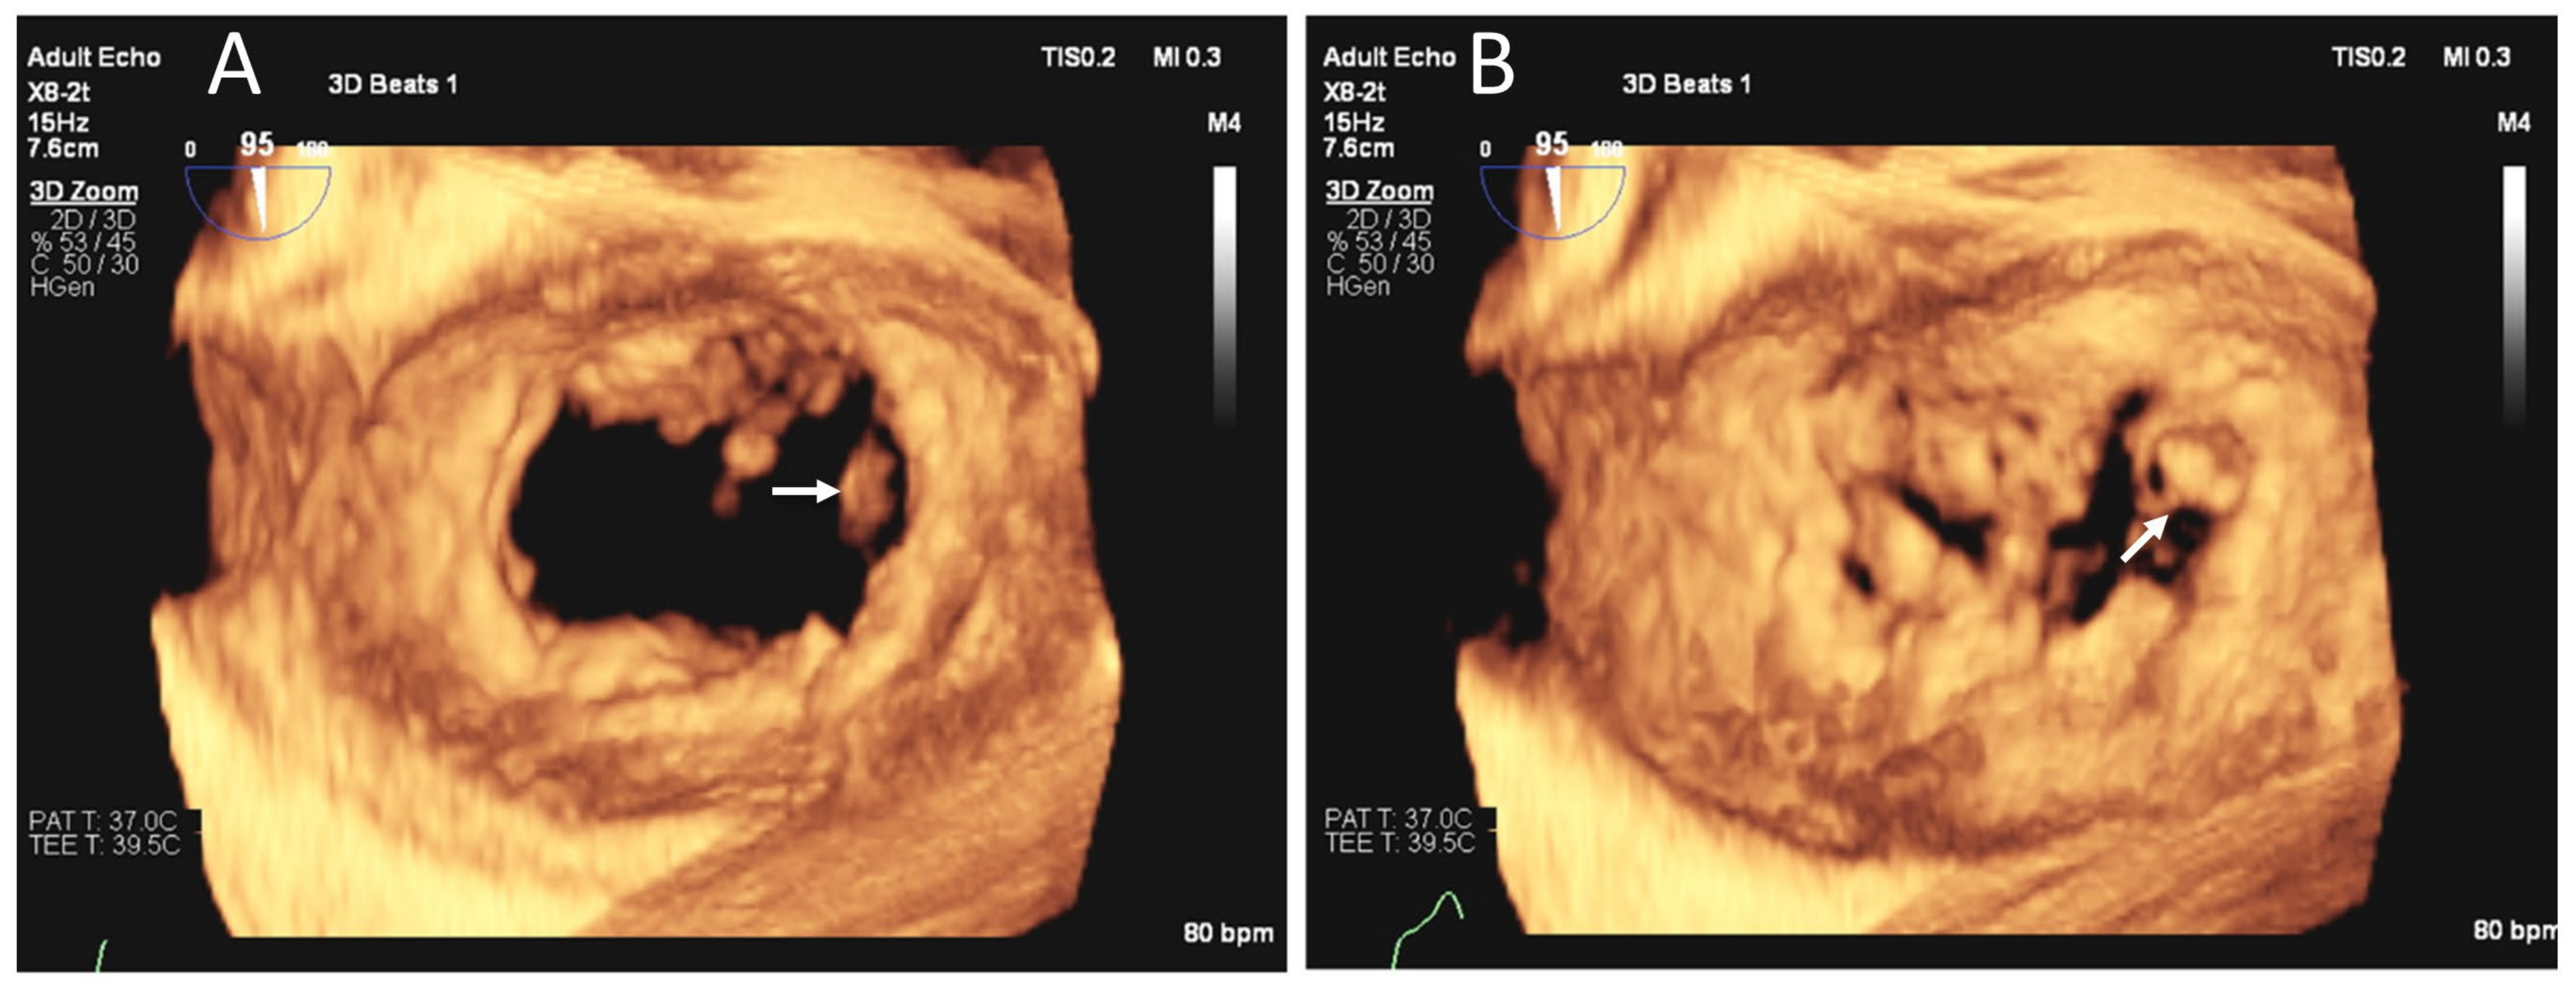

3.2. ≥Moderate Valvular Regurgitation

| Mitral regurgitation | 16 (20.8) | 17 (22.1) |

| Aortic regurgitation | 10 (13.0) | 11 (14.3) |

| Paravalvular leak on MV | 2 (2.6) | 2 (2.6) |

| Paravalvular leak on AV | 2 (2.6) | 2 (2.6) |